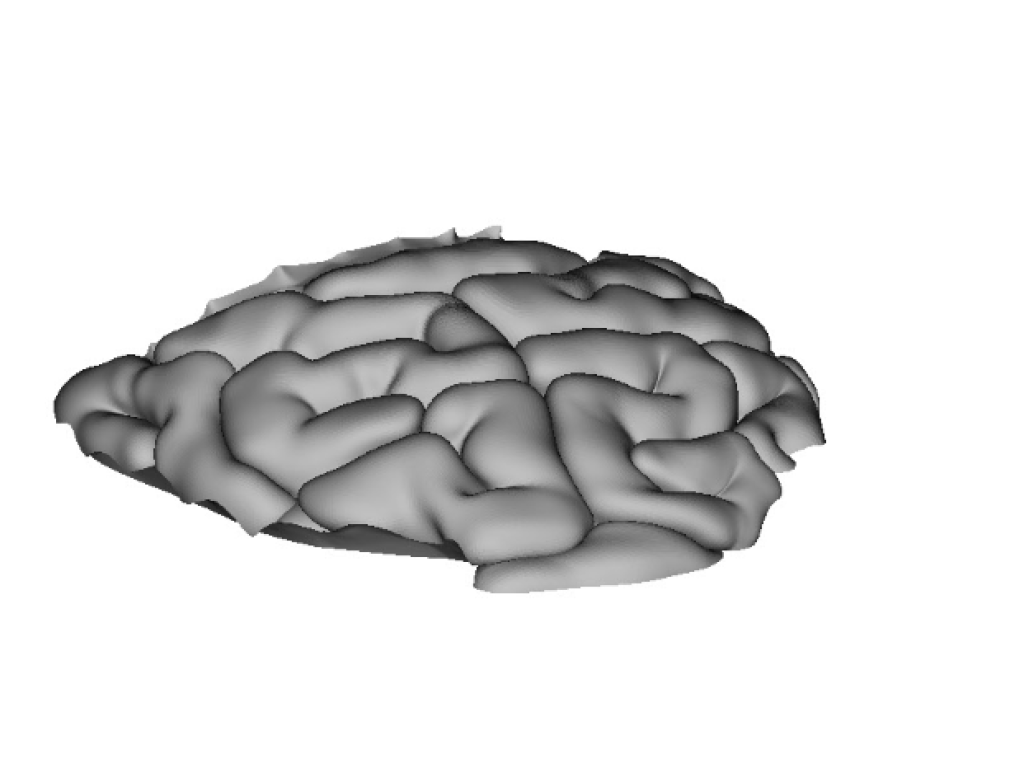

Модель Тонкий кишечник - часть 1 (начальный сегмент) применяется в медицине как элемент сборной модели туловища. Рекомендуемые материалы для печати данной модели: ABS.